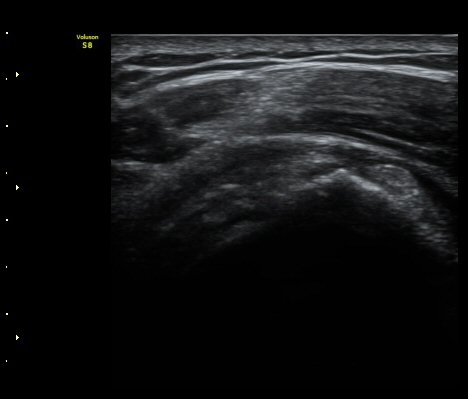

±Ø»ó°Ç ¸»´ÜºÎ Á¾´Ü¸é°Ë»ç¿¡¼­ ±Ø»ó°Ç°ú Á¡¾×³¶³» ¼®È¸È­°¡ °üÂûµÈ´Ù(±×¸² 4, 5).

ÆÄ¿öµµÇ÷¯°Ë»ç¿¡¼­ ±Ø»ó°Ç°ú Á¡¾×³¶ÁÖÀ§¿¡¼­ ¼ö¾×Àú·ù°¡ °üÂûµÈ´Ù(±×¸² 6, 7).